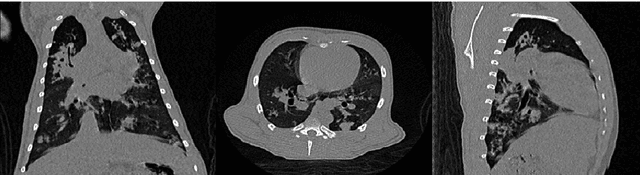

Tuberculosis (TB) is an infectious disease caused by Mycobacterium tuberculosis (Mtb.) that produces pulmonary damage due to its airborne nature. This fact facilitates the disease fast-spreading, which, according to the World Health Organization (WHO), in 2021 caused 1.2 million deaths and 9.9 million new cases. Fortunately, X-Ray Computed Tomography (CT) images enable capturing specific manifestations of TB that are undetectable using regular diagnostic tests. However, this procedure is unfeasible to process the thousands of volume images belonging to the different TB animal models and humans required for a suitable (pre-)clinical trial. To achieve suitable results, automatization of different image analysis processes is a must to quantify TB. Thus, in this thesis, we introduce a set of novel methods based on the state of the art Artificial Intelligence (AI) and Computer Vision (CV). Initially, we present an algorithm to assess Pathological Lung Segmentation (PLS). Next, a Gaussian Mixture Model ruled by an Expectation-Maximization (EM) algorithm is employed to automatically. Chapter 3 introduces a model to automate the identification of TB lesions and the characterization of disease progression. Chapter 4 extends the classification of TB lesions. Namely, we introduce a computational model to infer TB manifestations present in each lung lobe of CT scans by employing the associated radiologist reports as ground truth. In Chapter 5, we present a DL model capable of extracting disentangled information from images of different animal models, as well as information of the mechanisms that generate the CT volumes. To sum up, the thesis presents a collection of valuable tools to automate the quantification of pathological lungs. Chapter 6 elaborates on these conclusions.